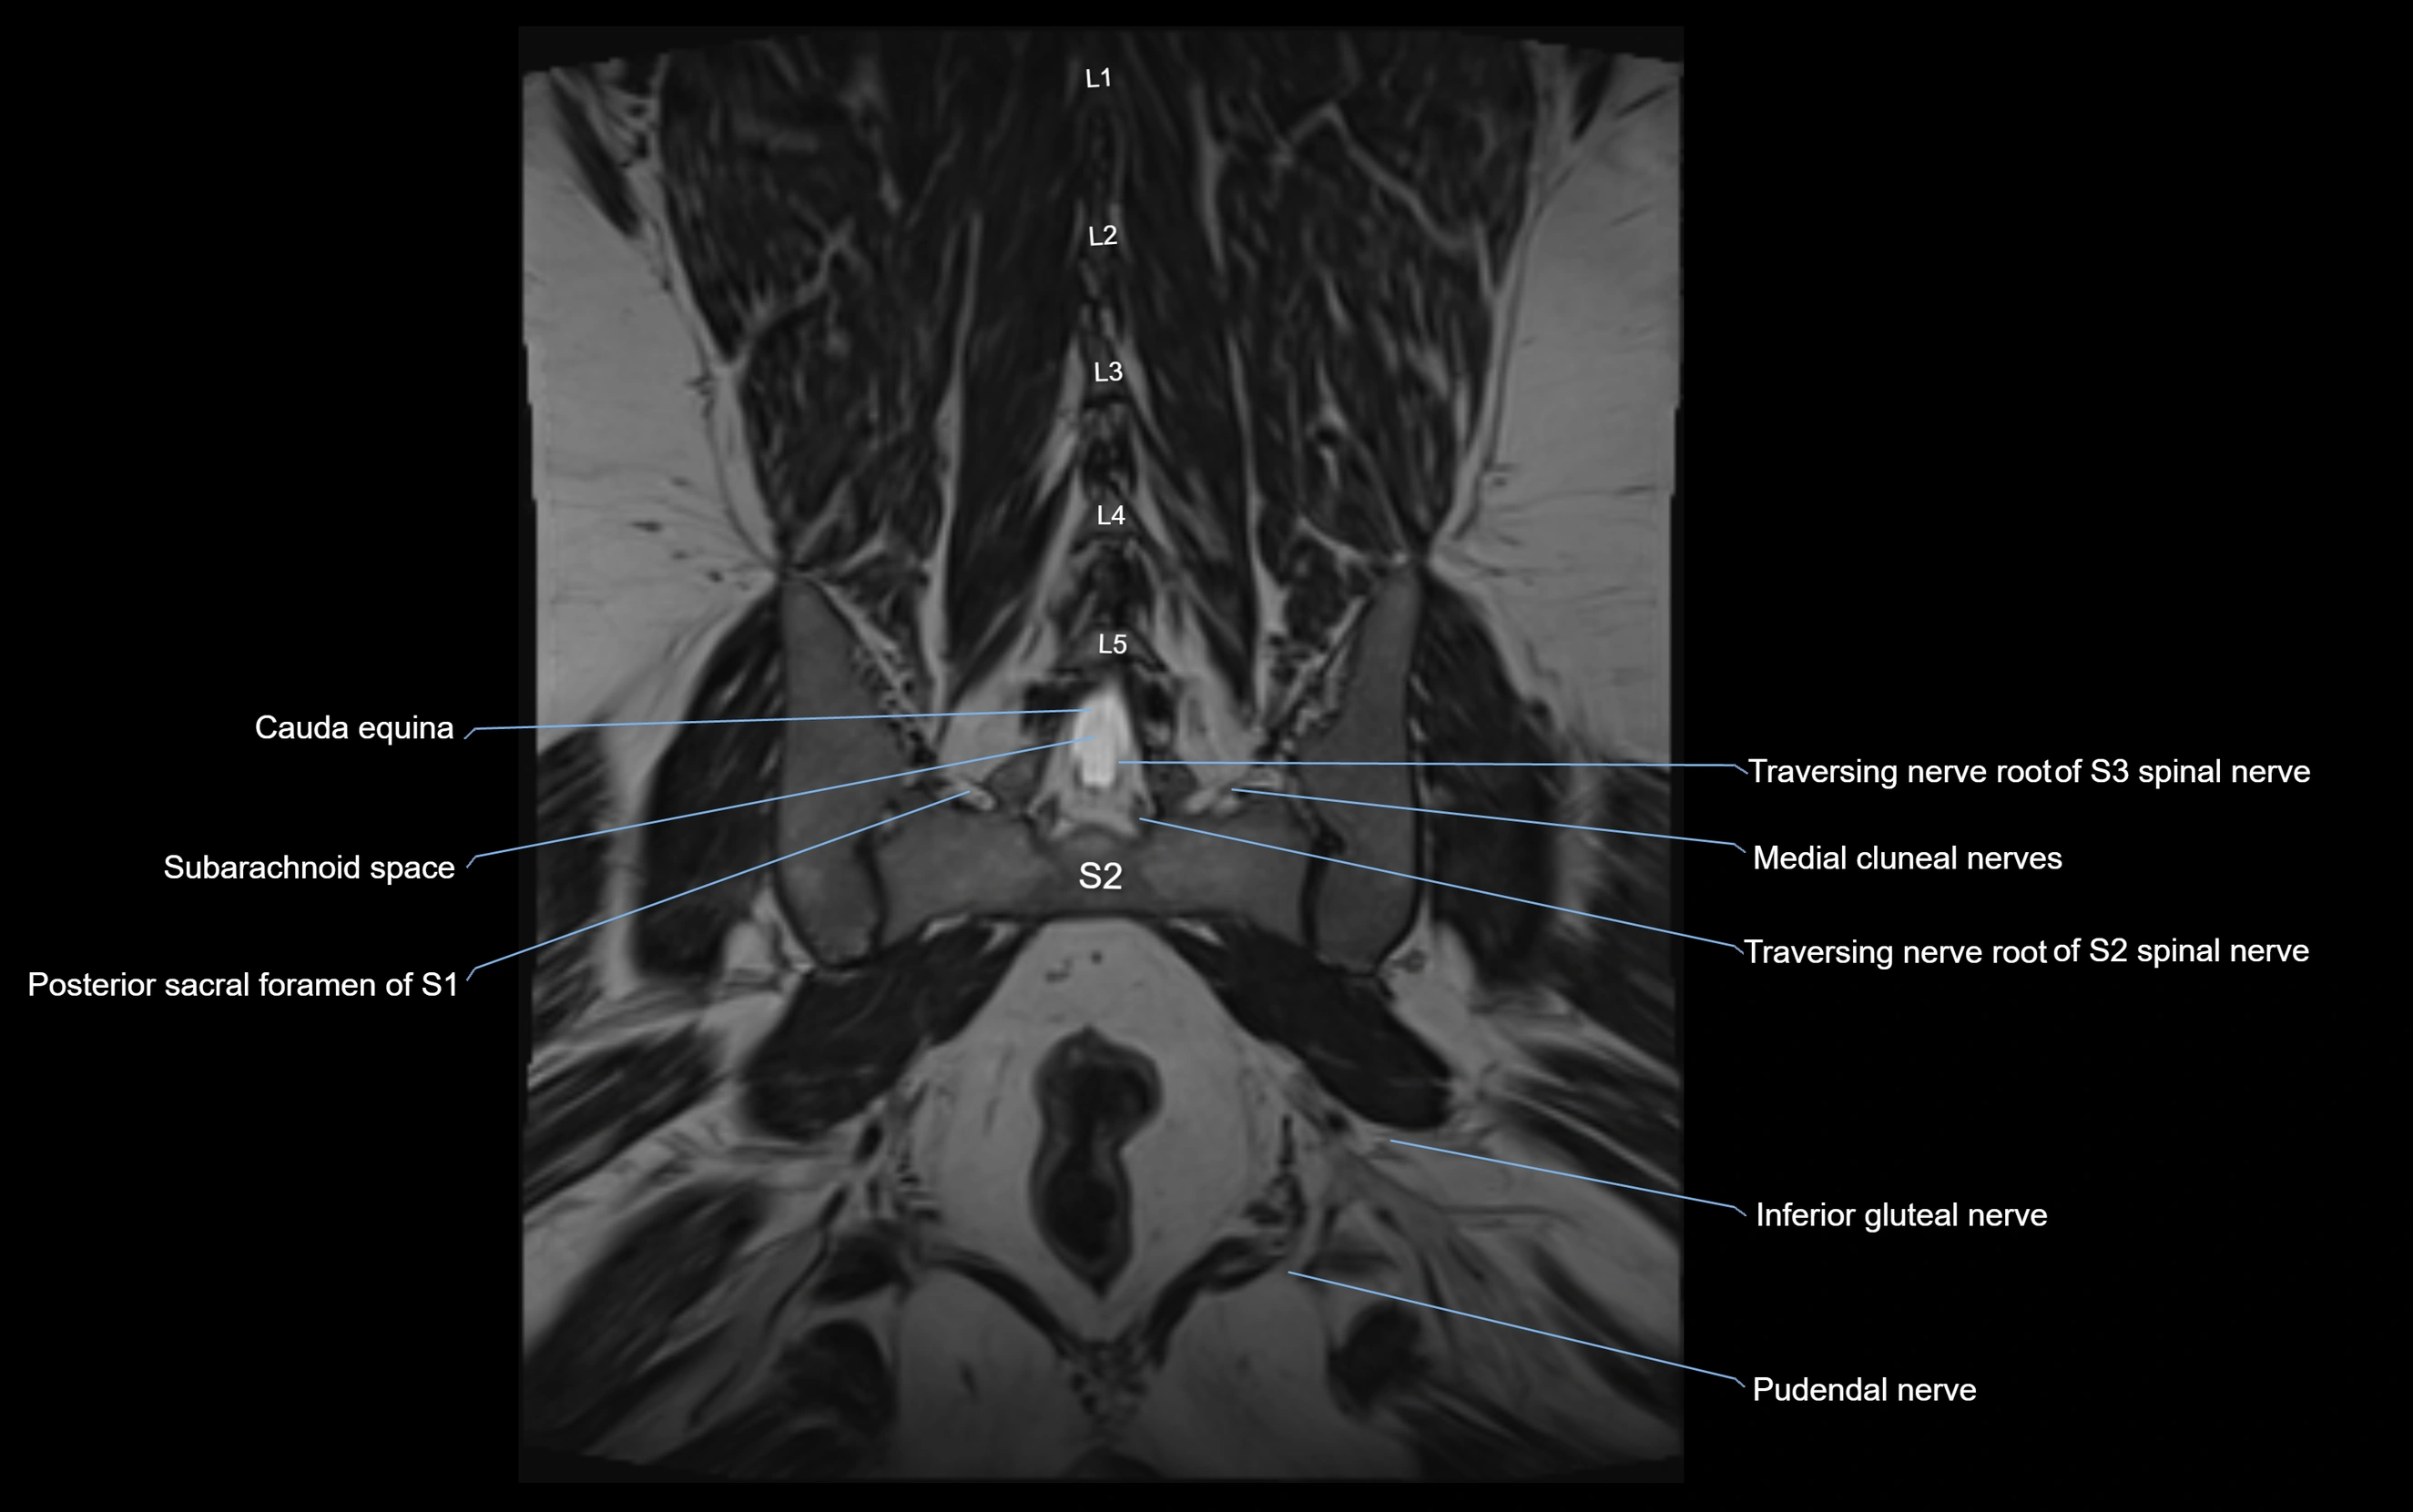

MRI Appearance

T1-weighted images:

• Nerve appears as a very thin low-to-intermediate signal intensity structure

• Surrounded by bright fat, aiding visualization

T2-weighted images:

• Nerve shows intermediate to mildly hyperintense signal compared to muscle

• Pathological involvement appears brighter

STIR (Short Tau Inversion Recovery):

• Normal nerve appears dark

• Inflamed or entrapped nerve appears bright hyperintense

T1 Fat-Sat Post-Contrast:

• Normal nerve enhances minimally

• Pathologic nerve (neuritis, entrapment, tumor infiltration) shows focal or diffuse enhancement

3D T2 SPACE / CISS:

• Nerve appears intermediate to mildly hyperintense compared to muscle

• Surrounded by bright fat or CSF, improving visualization

• Best sequence for mapping small pelvic nerves such as the anococcygeal